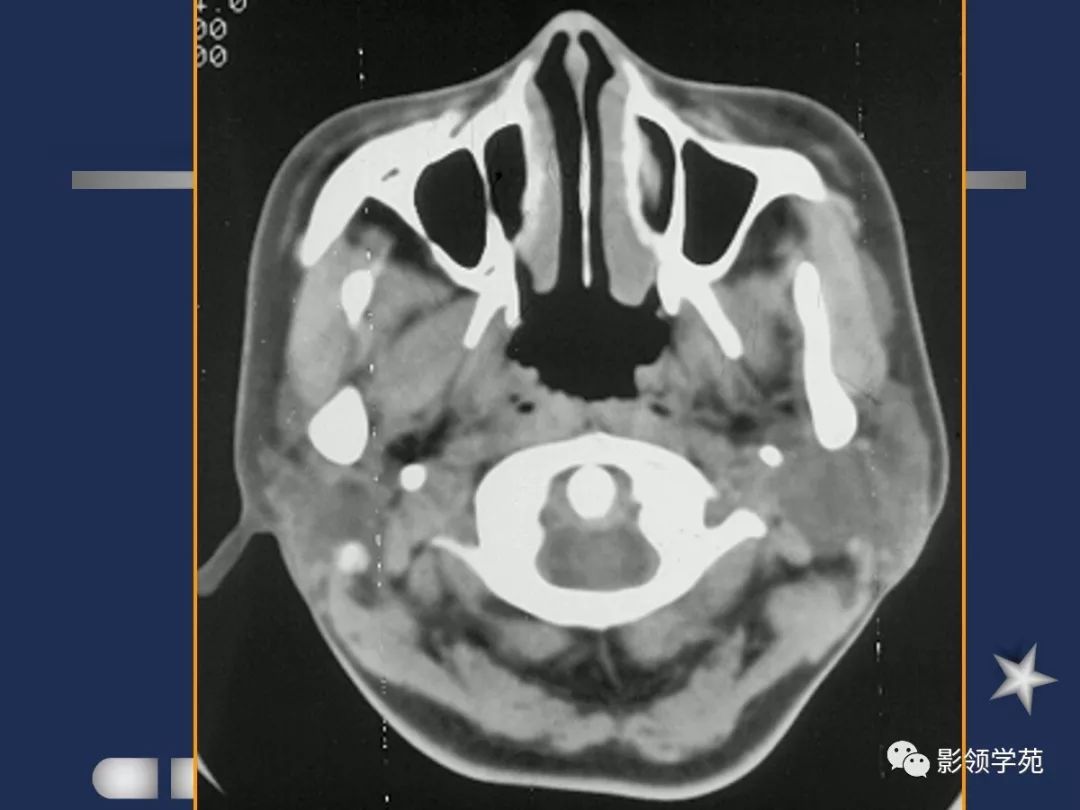

- 位于下颌骨后,胸锁乳突肌前,上致颅底,位于乳突尖和颞颌关节之间,下至下颌角,是茎突前咽旁间隙重要器官

- 腮腺是脂肪性腺体,CT呈低密度

- 腮腺内血管显示清楚